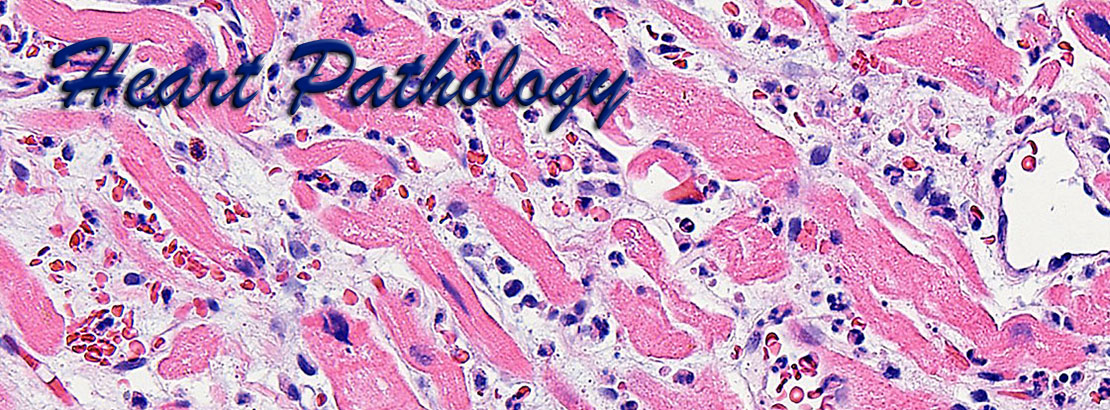

Cardiac pathology is an important area of pathology but is not comprehensively taught at many medical centers due to the paucity of cardiac specimens outside of the autopsy services. Our website uses high definition images obtained from gross pathology specimens and histological slides, both at a resolution of 1800x1350 pixels.

The images presented here represent a wide variety of heart pathology cases, including acquired diseases, transplantation pathology, idiopathic diseases, tumor pathology, etc., and are accompanied by brief morphological descriptions. The histological images are shown at different optical magnifications and include conventional stains such as hematoxylin-eosin, PAS, trichrome stains, as well as immunohistochemical stains. Also included are some images from normal tissues and from positive and negative controls for the corresponding special stains.